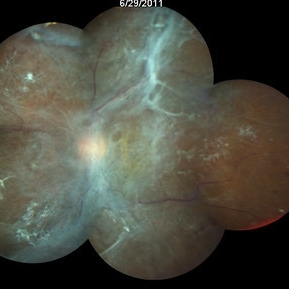

Fundus photo shows classic 'tomato-ketchup' red appearance of diffuse hemangioma. Due to chronic SRF , there is subretinal fibrosis.

Condition/keywords: subretinal fibrosis